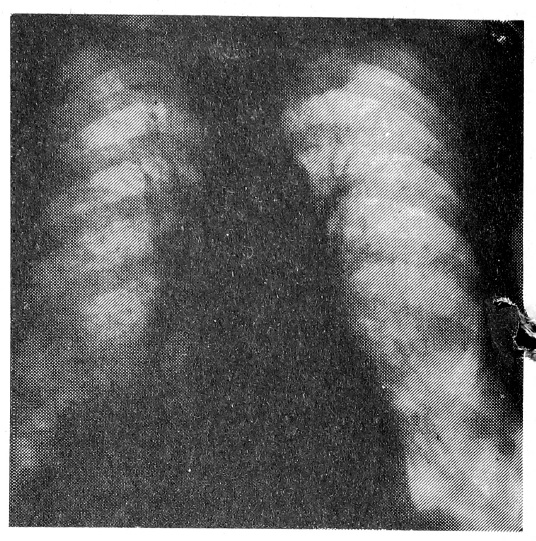

На рентгенограмме органов грудной клетки в прямой проекции в зоне переднебазального сегмента нижней доли правого легкого было определено тенеобразование неправильной формы, с неровными контурами, дорожкой перибронхиального уплотнения к корню (рис. 1). При катетеризации бронхов 03.02.1988 г. управляемый катетер был проведен в устье переднебазального бронха — аспирировано небольшое количество гнойной мокроты. Через телескопический катетер, продвинутый в толщу тенеобразования, было накачано до 20 см3 кислорода, при этом выявлена полость распада и стали отходить обильные гнойные массы. После очистки полости распада с ее внутренней стенки был взят материал для цитологического исследования; введено около 3 мл верографина, позволившего определить дно полости (рис. 2). Заключение цитолога: картина высокодифференцированного эпидермоидного рака легкого.

Рис. 1. В зоне С-8 правого легкого определяется средней интенсивности однородная, округлой формы тень размером до 8 см в диаметре с неровными нечеткими контурами.

Рис. 2. На рентгенограммах правого легкого того же больного в прямой (а) и правой боковой (б) проекциях виден управляемый катетер в просвете промежуточного бронха. По нему проведен телескопический катетер через Б-8 в толщу тенеобразования. После введения воздуха стала дифференцироваться полость деструкции с неровными внутренними контурами. На дне полости определяется контрастное вещество.

Таким образом, при отсутствии признаков распада по данным рентгенотомографии наш метод позволил не только выявить наличие полости деструкции в толще тенеобразования с характерными для рака внутренними контурами, но и получить цитологическое подтверждение диагноза, визуализировать протяженность распространения опухоли.